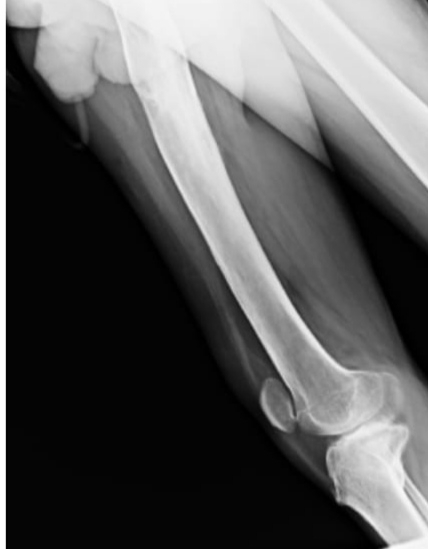

-H/o RTA 3 Years ago after which he got implant in right tibia.

Orthopedic referal taken for stiffness in right knee , chronic Osteomyelitis?,

Opinion of orthopedic:

Extra articular ankylosis

Quadriceps contracture

And suggested for SURGICAL CORRECTION OF QUADRICEPS PLASTY FOR FLEXION OF KNEE